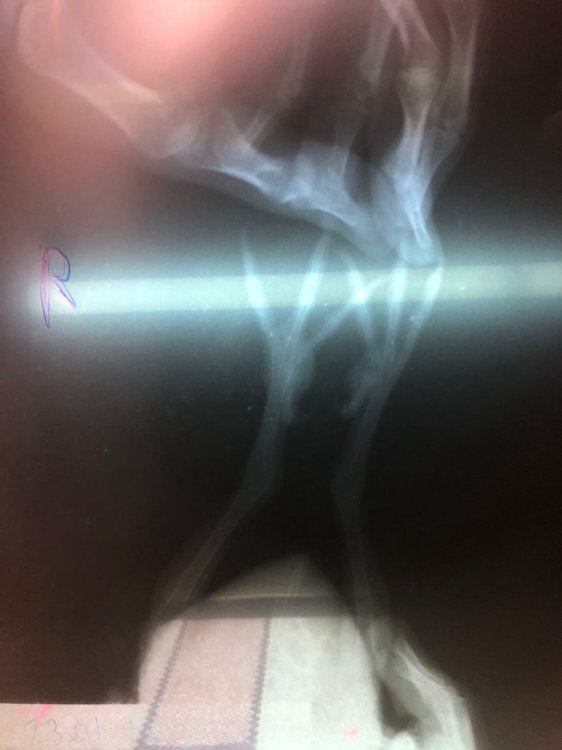

Juan_Esteban_Vazquez Опубликовано 23 февраля, 2022 Автор #87 Опубликовано 23 февраля, 2022 @Zosia, здравствуйте. Сегодня сделали рентген. Скрытый текст

Juan_Esteban_Vazquez Опубликовано 25 февраля, 2022 Автор #88 Опубликовано 25 февраля, 2022 Всем привет. Сегодня заметил, что шишка на правой лапке как-то изменил свой вид и кажется вышел наружу. Такое бывает при подагре? Скрытый текст